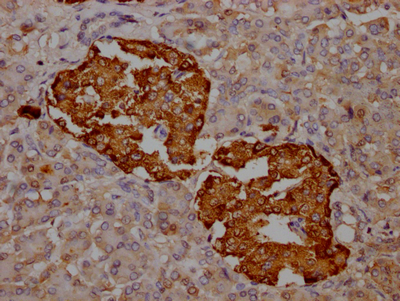

IHC image of CSB-RA588381A0HU diluted at 1:100 and staining in paraffin-embedded human pancreatic tissue performed on a Leica BondTM system. After dewaxing and hydration, antigen retrieval was mediated by high pressure in a citrate buffer (pH 6.0). Section was blocked with 10% normal goat serum 30min at RT. Then primary antibody (1% BSA) was incubated at 4℃ overnight. The primary is detected by a Goat anti-rabbit IgG polymer labeled by HRP and visualized using 0.05% DAB.